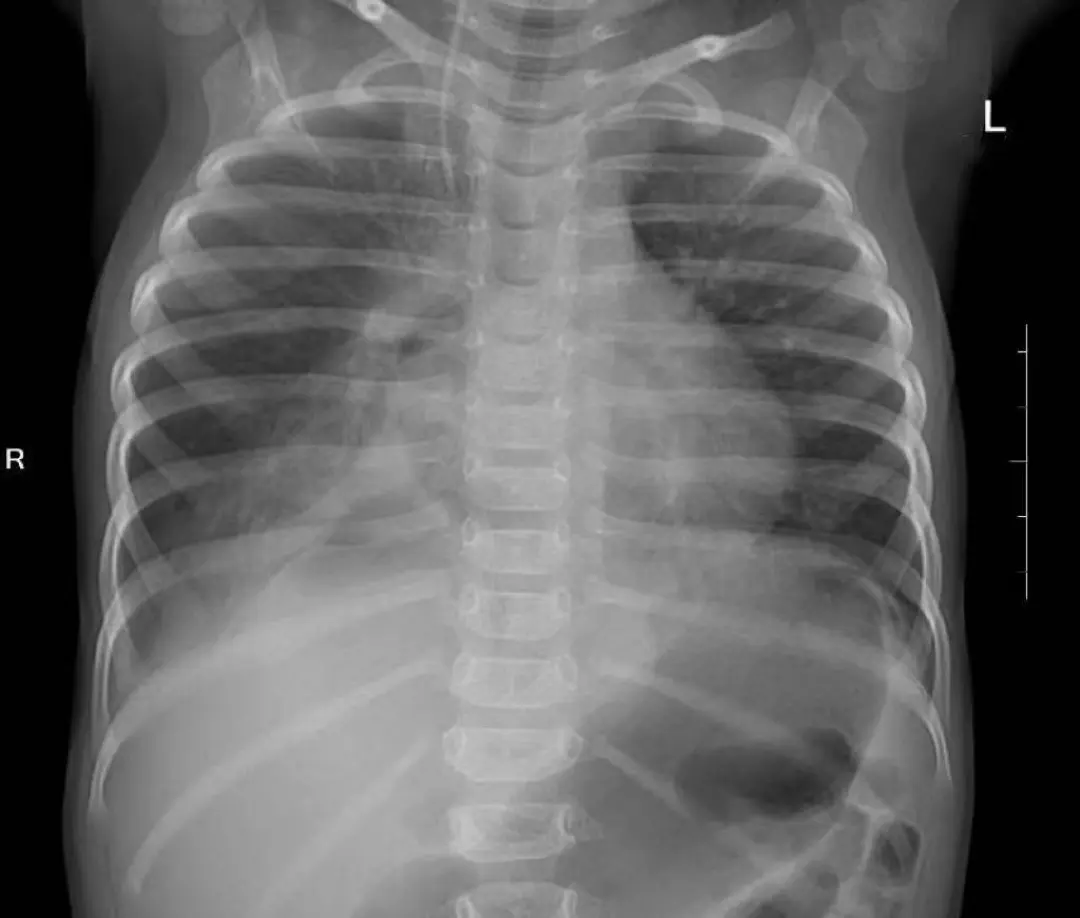

据了解,依依一个多月来反复出现吃奶后呕吐、腹泻,焦急的家人带她到当地医院就诊,为了查清病因,医生为她安排了腹部CT检查。结果却出乎所有人的意料——依依的胃,竟然不在它应该在的腹腔里,而是穿过分隔胸腔和腹腔的肌肉层,“跑”进了右侧胸腔。

这个意外发现让家人意识到问题的严重性。为了明确诊断,他们带着依依来到湘雅医院。进一步的检查确认,依依患的是一种先天性结构畸形,叫做“食管裂孔疝”,同时还伴有胃-食管反流。正常情况下,食管穿过膈肌进入腹腔的那个通道,在依依身上变得异常宽大,以至于胃,甚至部分结肠都从这个缺口挤进了胸腔。这不仅导致她吃进去的食物无法正常消化吸收,引起呕吐和营养不良,更严重的是,移位的内脏还压迫了她的右肺,导致肺叶无法充分张开,甚至引发了肺部感染。

经过充分的术前准备,一场微创手术在麻醉科和手术室的默契配合下展开。小儿外科团队联合胸外科,为依依实施了腹腔镜下食管裂孔疝修补术加胃底折叠术。手术仅在依依的腹壁上开了三个3毫米和一个5毫米的微小切口。术中,医生清晰地看到,除了胃,还有一部分结肠也经扩大的裂孔钻进了右侧胸腔。他们精准地将这些脏器一一归位,关闭了那道异常宽大的食管裂孔,并巧妙地用胃底折叠重建了一个抗反流的“阀门”,从根源上解决了依依胃食管反流的问题。

手术效果立竿见影。术后第一天,依依开始进食,困扰她一个多月的呕吐消失了。术后第三天复查,受压的右肺已完全张开。术后一周,依依顺利康复出院。